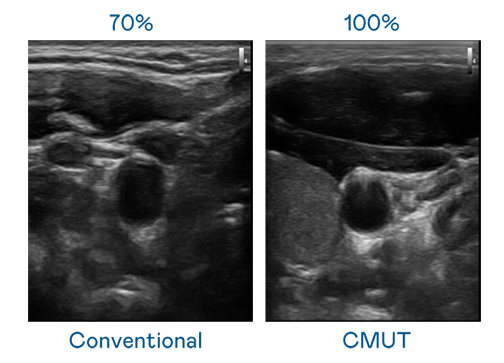

CMUT 技术是一种用电容式微机电元件来产生超音波讯号的技术。与传统 PZT 压电式技术相比,CMUT 频宽增加 30%,更宽频的超音波讯号让影像解析度大幅提升,是实现高影像品质医疗超音波扫描、促进精准医疗发展的关键技术。

大频宽带来超清晰影像

超音波影像的解析度高低,首先取决于探头能发出的讯号频宽。圣淘沙 CMUT 可提供高清晰的超音波讯号,提供高频宽、高灵敏度、影像纹理细节更高的超音波影像,协助医护人员缩短影像判读时间及利用精准的医疗影像进行诊断。